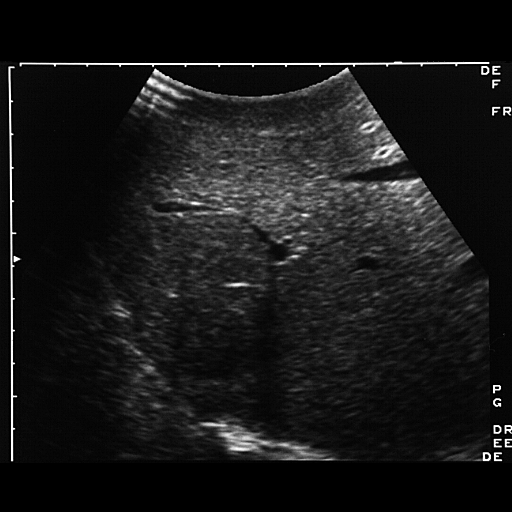

HISTORY: Rectal carcinoma.  Intraoperative evaluation of liver mets.

FINDINGS: Images 1-4 are intraoperative sonograms of the liver to

evaluate for metastases.  Images 1-3 demonstrate a 3 x 5 cm hypoechoic

mass seen abutting the diaphragm in the junction of the anterior and

posterior segments of the right lobe (arrows).  Note the right hepatic

vein in Images 2 and 3.  On Image 11 there is clear evidence of

refractive edge shadowing from the lesion.  On Image 4 there is a very

subtle hypoechoic lesion which was an additional satellite nodule seen

high up near the diaphragm (arrows).  Surgical resection of this lesion

confirmed an additional metastatic deposit.

DIAGNOSIS: Hepatic metastases from rectal carcinoma.